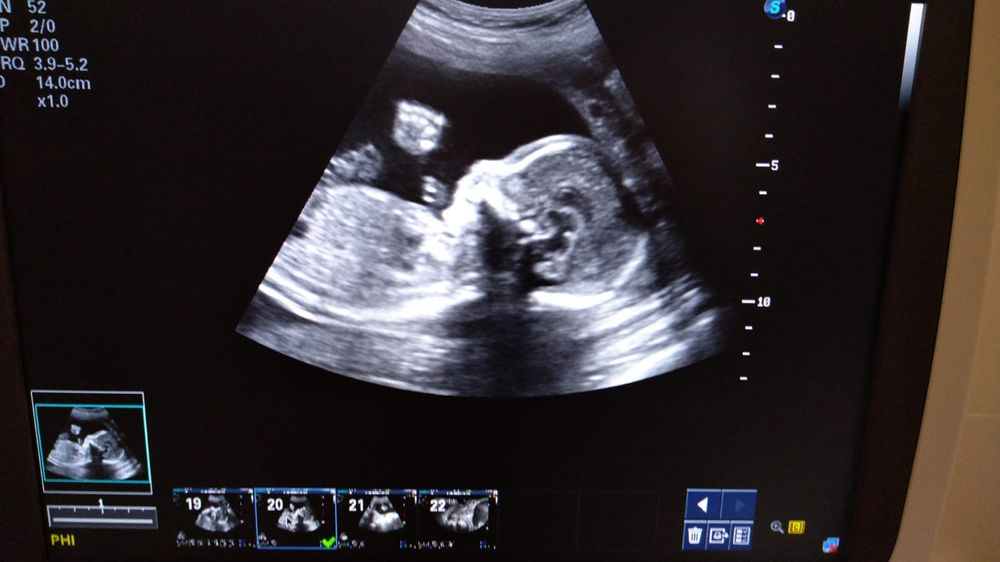

Таблица БПР (бипариетальный размер головки плода) по неделям беременности представляет собой инструмент для отслеживания развития плода. Она содержит информацию о средних значениях БПР на разных сроках беременности и помогает оценить соответствие размеров головы плода установленным нормам. Таблица может быть использована врачами для мониторинга беременности и выявления возможных отклонений в развитии плода.